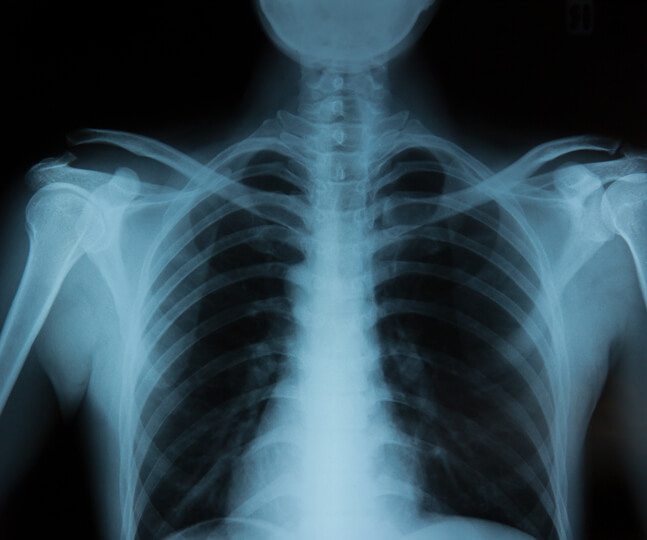

Digital X-ray

Digital radiography (DR) is an advanced form of x-ray inspection which produces a digital radio graphic image instantly on a computer. This technique uses x-ray sensitive plates to capture data during object examination, which is immediately transferred to a computer without the use of an intermediate cassette. Elitecare Hospital has 24X7 digital X-ray facility .